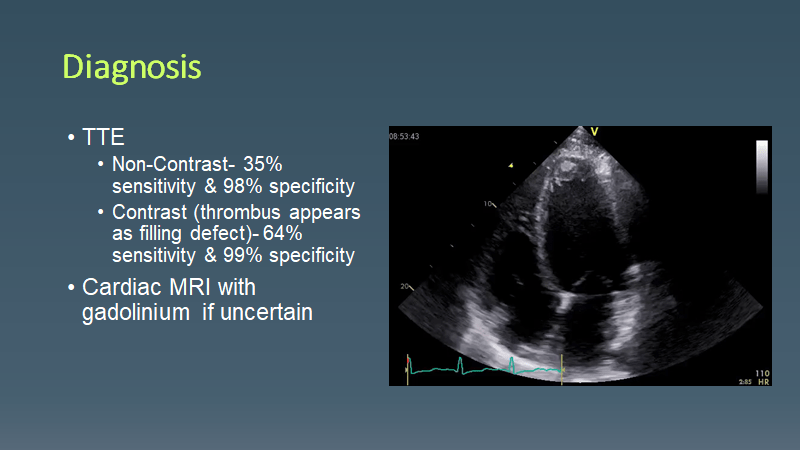

Morning Report LV Thrombus March 15, 2021 vmcimchiefs Leave a comment Today we had a case of pt with HFrEF who presented with an ACS event c/b LV thrombus causing RLE occlusion requiring amputation Share this: Share on X (Opens in new window) X Share on Facebook (Opens in new window) Facebook Like Loading... Related